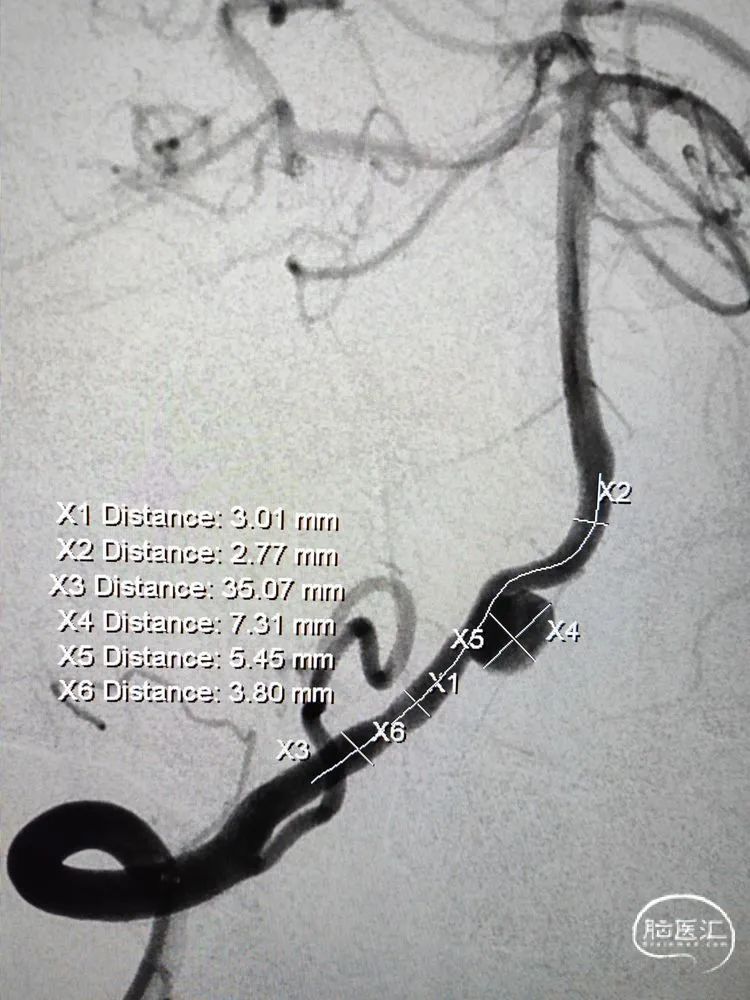

术前影像学检查:全脑血管造影检查提示右侧椎动脉V5段(颅内段)夹层动脉瘤。

动脉瘤大小约5.45mm×7.31mm,动脉瘤远端椎动脉汇合前管径约2.77mm,动脉瘤近端V4段管径约3.80mm,V5段全长约35mm,对侧椎动脉正常。

测量数据